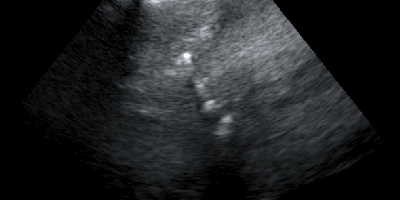

Κατηγορία: Abdominal Ultrasound